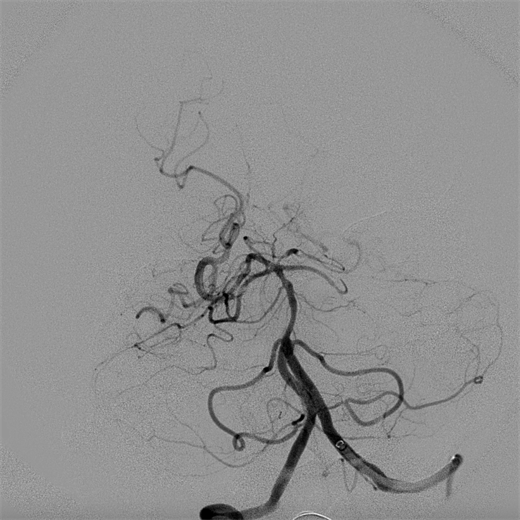

手术中,神经内科三病区主任张振昶取栓团队急诊实施了全麻下脑血管造影术和经导管颅内血管血栓去除术,从股动脉穿刺到血流复通仅用时13分钟,顺利取出1枚大小约3mm*6mm的暗红色血栓。术后,患者逐渐清醒,四肢可自主活动,经神经内科ICU的精心监护、高效治疗,术后第三天患者意识完全恢复正常,肢体活动自如,mRS评分0分,已具备回归正常工作生活的能力,全体医护人员精湛的医疗技术和精心的护理获得了患者和家属的一致好评。

术后